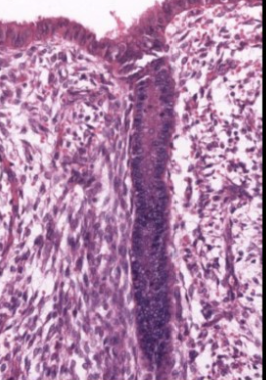

ciliated cell histology

can see basal body (dark line under cilia)

peg cell histology

no basal bodies, protrusions off apical surface